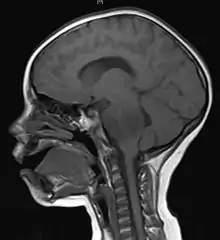

Meninges

Human brains are surrounded by a system of connective tissue membranes called meninges that separate the brain from the skull. This three-layered covering is composed of (from the outside in) the dura mater, arachnoid mater, and pia mater. The arachnoid and pia are physically connected and thus often considered as a single layer, the leptomeninges. Between the arachnoid mater and the pia mater is the subarachnoid space which contains cerebrospinal fluid (CSF). This fluid circulates in the narrow spaces between cells and through the cavities in the brain called ventricles, to support and protect the brain tissue. Blood vessels enter the central nervous system through the perivascular space above the pia mater. The cells in the blood vessel walls are joined tightly, forming the blood–brain barrier which protects the brain from toxins that might enter through the blood.[32]

The brains of humans and other vertebrates are composed of very soft tissue and have a gelatin-like texture. Living brain tissue has a pink tint in color on the outside (gray matter), and nearly complete white on the inside (white matter), with subtle variations in color. The three largest divisions of the brain are:

The brainstem lies between the large cerebral cortex and the spinal cord. It is divided into the midbrain, pons, and medulla oblongata.[32]